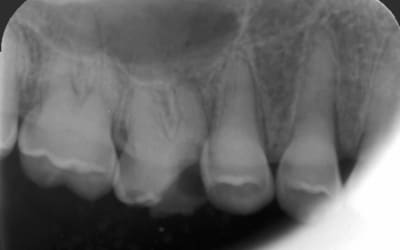

Radio 11

8af24b3d fd05 4021 a759 7a5e9e05a6a7 h5jlk1 - Eugenol

poignée de porte a diagnostiqué une maladie genetique, c'est un cas d'amélogenèse imparfaite avec racines courtes, obliteration des chambres pulpaires, émail fin et de mauvaise minéralité pour du collage... necrose en lien avec l'usure (les incisives inf)